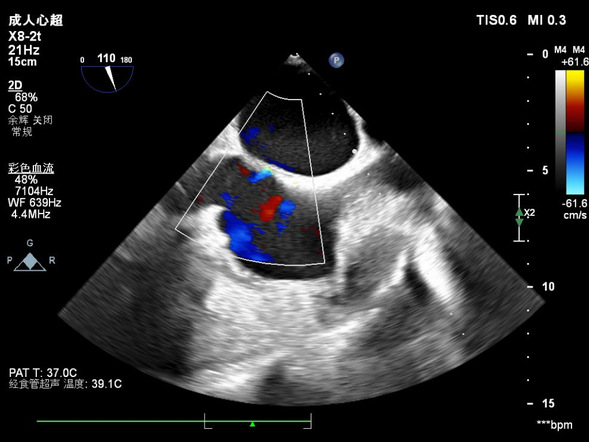

赵某,男,68岁,既往房颤病史3年,临床射频消融术之前完善食道超声检查,食道超声明确诊断:左心耳血栓。临床为左心耳血栓患者及时进行了溶栓治疗,避免了患者因血栓脱落引起的严重并发症。

超声科进行经食道超声心动图检查